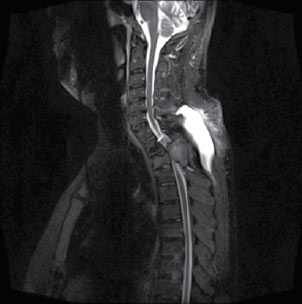

Dentro de los casos reportados, es usual que se realizaran múltiples estudios para enfocar la lesión entre los cuales se encuentran: radiografías en las que se observan lesiones líticas únicas o múltiples mal demarcadas en expansión, además de desmineralización generalizada. Por otro lado, la tomografía muestra mejor definición de la erosión local y extensión presentada no solo en hueso sino también en tejido blando, que se intensifica con el medio de contraste; sin embargo, no es específica para diagnosticar este tipo de tumores, porque no los distingue de otro tipo de lesiones. Por último, la Resonancia Magnética es de gran ayuda en la mejor caracterización de las lesiones y su extensión, éstas se ven usualmente hipointensas en la secuencia de T1, hiper o hipointensas en la secuencia de T2 (esto se lo debe al grado de su componente quístico), con realce posterior a la administración del medio de contraste por su alta vascularización, la formación de hemorragias intratumorales que generan niveles líquido-líquido. El compromiso en columna se caracteriza por ser de componente sólido, que frecuentemente causa destrucción de la corteza y extensión a tejidos blandos (figuras 1 al 4)(5).

| Figura 3. Imagen de la izquierda: secuencia T1. Imagen de la derecha: secuencia T2. Ambas sin contraste, corte sagital. En las imágenes se aprecia lesión que causa disminución de la amplitud del canal vertebral y compresión del canal medular, que se ve con mayor exactitud en secuencia T2, donde se resalta el espacio medular. Además, se observa, cambios en la altura del cuerpo vertebral |